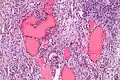

Micrograph of a struma ovarii. Characteristic thyroid follicles are seen on the right, and ovarian stroma on the left. H&E stain.

A struma ovarii (literally: goitre of the ovary) is a rare form of monodermal teratoma that contains mostly thyroid tissue, which may cause hyperthyroidism.[1]